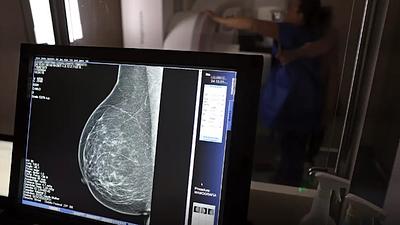

Câncer de mama atinge uma em cada três mulheres com menos de 50 anos

Para a intituição, os números reforçam a importância de ampliar o rastreamento do câncer de mama por meio da realização de mamografia em mulheres abaixo dos 50 anos e acima dos 70 anos.